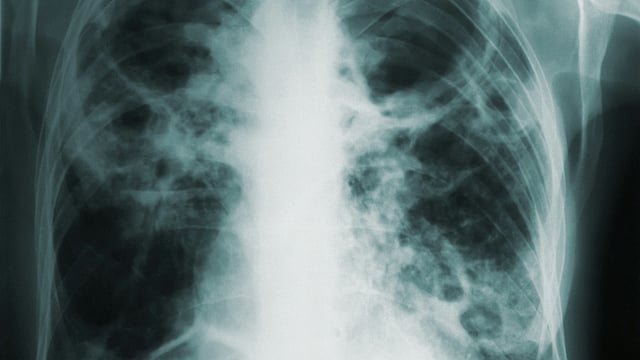

Tuberculosis bacteria multiply and can cause symptoms like cough, night sweats, fever and weight loss. Skin or blood tests will likely be positive and radiography (e.g., chest X-ray or CT scan) will be abnormal. Image source: Unsplash

Active TB disease is when TB bacteria multiply and can cause symptoms like cough, night sweats, fever and weight loss. Skin or blood tests will likely be positive and radiography (e.g., chest X-ray or CT scan) will be abnormal.